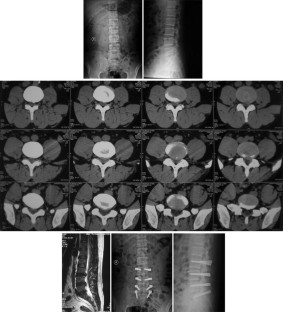

Fig. 1

Fig. 2